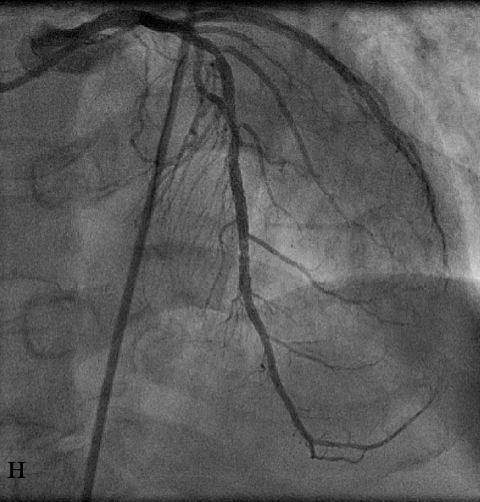

В связи с наличием выраженного пролонгированного стеноза на границе среднего и дистального сегментов ПМЖВ (м) в область сужения был имплантирован стент Cypher с хорошим ангиографическим результатом (н).